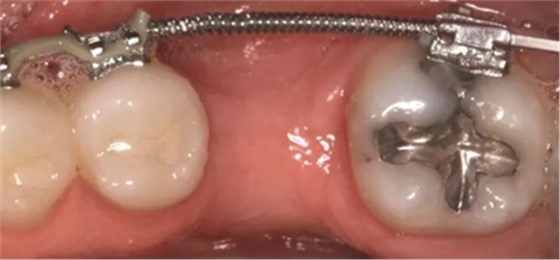

圖2d. 3個(gè)月后,獲得顯著的骨增量,同時(shí)創(chuàng)造出1.6mm的近遠(yuǎn)中修復(fù)空間

術(shù)后即刻,將0.018×0.025英寸的銅鎳鈦(NiTi)弓絲和NiTi 主弓絲套推簧沿著無(wú)牙頜區(qū)域置于雙側(cè),施加半托槽寬度(約1.5mm)的力?;颊咴谧畛醯?個(gè)月中,每2周隨訪(fǎng)一次,之后每月隨訪(fǎng)一次。1個(gè)月后,左側(cè)下頜第一磨牙區(qū)獲得了10mm的近遠(yuǎn)中距離,用被動(dòng)線(xiàn)圈保持。對(duì)側(cè)區(qū)域(右側(cè)第一磨牙)空間通過(guò)主弓絲套推簧和三線(xiàn)圈來(lái)加力(一個(gè)托槽的寬度)。術(shù)后3個(gè)月時(shí),達(dá)到10mm的目標(biāo)(圖2d)。分別在術(shù)前(圖3a)和骨增量5個(gè)月后(圖3b)拍攝右下頜第一磨牙區(qū)域的錐束CT,結(jié)果顯示,成功獲得了5mm的水平骨增量。這樣的增量允許在合適的位置上植入一個(gè)寬直徑的種植體。